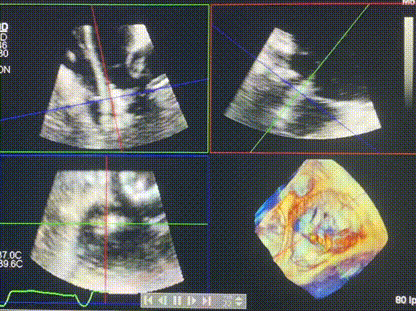

術(shù)中輸送器在超聲引導(dǎo)下調(diào)整位置

手術(shù)在全麻狀態(tài)下進行。術(shù)者采用經(jīng)右側(cè)頸靜脈入路的方式將輸送器送入患者心臟內(nèi),在TEE及DSA引導(dǎo)下調(diào)整輸送器頭端角度,使得輸送器與三尖瓣瓣環(huán)平面垂直。在輸送器進入右心室后釋放室間隔錨定裝置,而后釋放瓣葉夾持件(2個耳片結(jié)構(gòu))成垂直狀態(tài)。在TEE及DSA確定夾持件固定至三尖瓣葉根部且位于右室側(cè)后釋放人工瓣心房側(cè)盤片。隨后調(diào)整瓣膜同軸性以及室間隔錨定件位置(貼合室間隔),前推藏針管并固定,進而釋放室間隔錨定裝置,并再次確認瓣膜位置、穩(wěn)定性及同軸性,合攏輸送鞘后撤出輸送器,完成LuX-Valve Plus人工三尖瓣瓣膜的植入,僅殘余微量瓣周漏。且經(jīng)手術(shù)中心電生理團隊評估,病人的起搏器和ICD功能沒有受到影響。